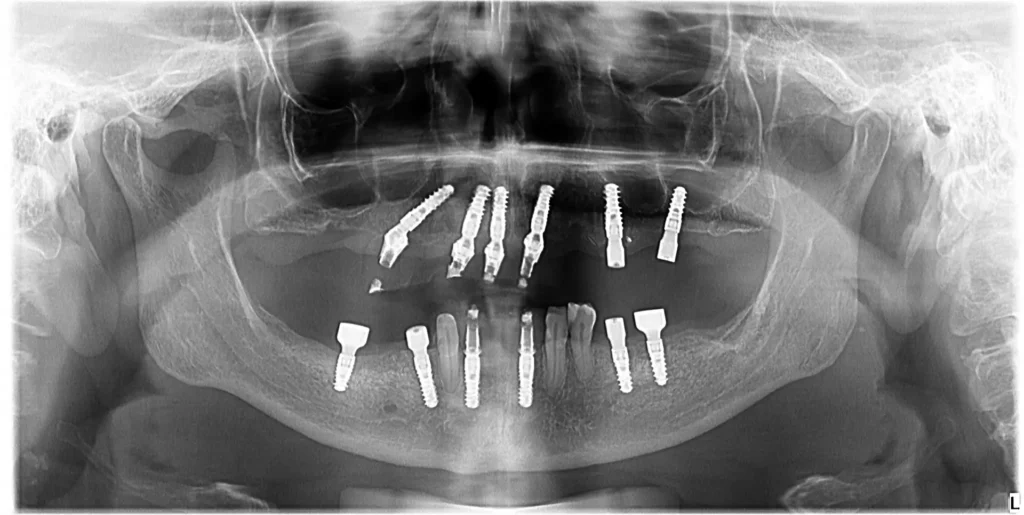

Am recomandat extractia dintilor irecuperabili, all on 6 la maxilar, conservarea unor dinti la mandibula si reabilitari protetice pe implanturi in zonele laterale si zona frontala.

- Am efectuat o reabilitare completa prin inserarea a 6 implanturi la maxilar. In 24 de ore, a primit o lucrare provizorii fixa, care a asigurat funcționalitate și estetică imediată.

Sistemul All-on-6 este o varianta sigura si predictibila pentru a reabilita cavitatea orala. Acum avem un pacient fericit, cu un zâmbet impecabil. orala complexă (refacerea funcției masticatorii, estetice).